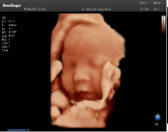

4容積探頭

積探頭是在二維圖像的基礎(chǔ)上,將連續(xù)采集的空間分布位置,經(jīng)過計(jì)算機(jī)重建算法,從而獲得完整的空間形態(tài)。

適用于:胎兒面部、脊柱和肢體等。

優(yōu)勢特點(diǎn):快速獲取、掃查連續(xù)均勻、解剖結(jié)構(gòu)顯示為容積數(shù)據(jù)、準(zhǔn)確進(jìn)行容積測量。